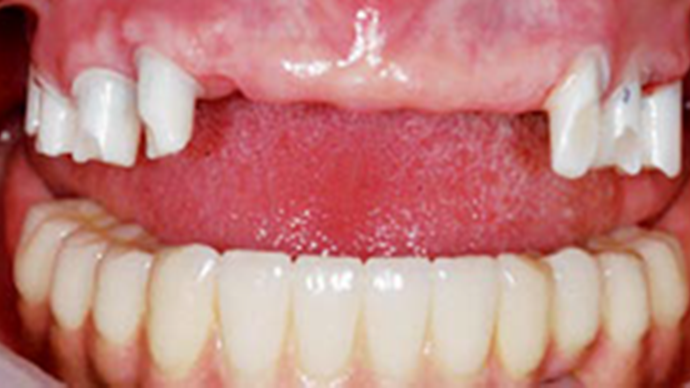

Clinical case: AFull transition from natural teeth to all-on-6 bridges

with AnyRidge implants

- Courtesy of Dr. Rabih Abi Nader, UAE -

“AnyRidge ensures long-term biological stability

& functionality even in

full-mouth rehabilitation case. ”